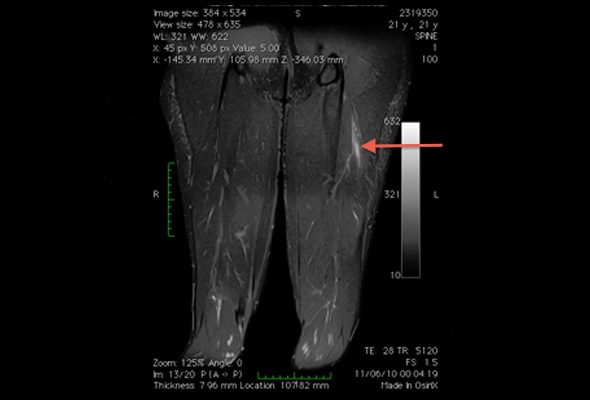

Lesão muscular da cabeça curta do bíceps.

Atleta de 21 anos com dor súbita na coxa durante corrida de velocidade. Lesão muscular grau 2 na cabeça curta do bíceps (corte coronal STIR)